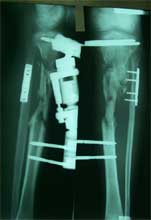

异体皮质骨用来桥接骨缺损,异体松质骨与自体红骨髓复合

胫骨上段骨折术后1年,骨缺损、骨不连

异体皮质骨桥接骨缺损,异体松质骨与自体红骨髓复合后,填充入间隙中。

术后1年,骨折愈合